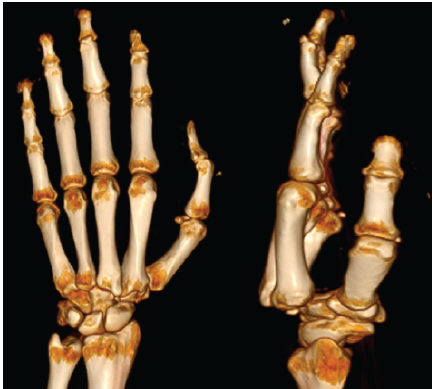

He was managed with analgesics, a crepe bandage, and limb elevation initially for 2 days before reporting to the hospital. Plain radiographs of the left-hand anteroposterior and lateral views revealed dorsal CMC dislocations of all four fingers of the ulnar side of the left hand (Fig. 2). An oblique view of the left hand was taken to confirm the diagnosis. A 3D computed tomography (CT) scan was done to rule out fracture-dislocations (Fig. 3).

Figure 3: Representative 3D computed tomography scan showing dislocation without any fractures.